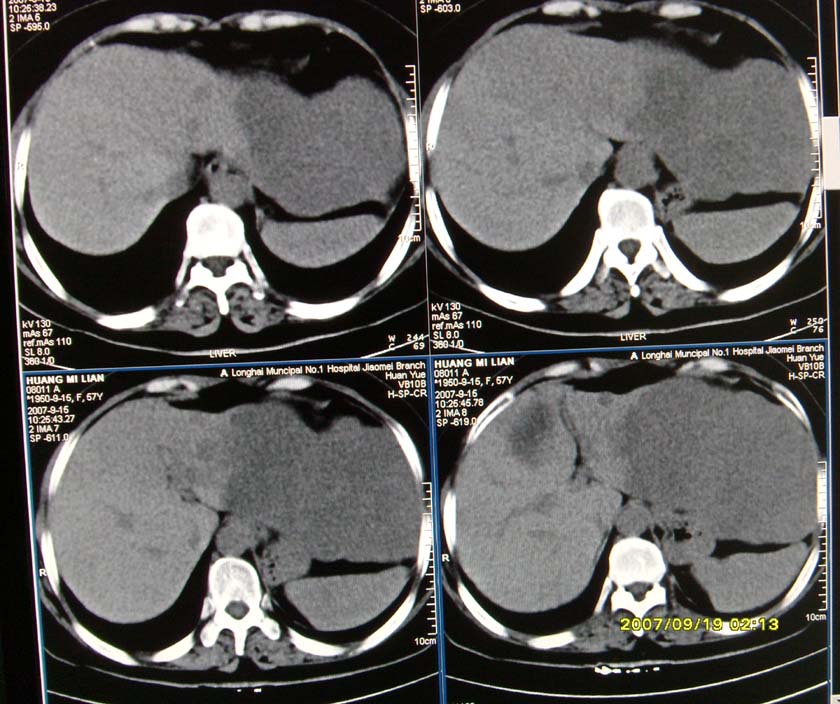

以下是引用逸风在2007-9-19 20:11:00的发言:[br]定位在肝左叶应该没有问题![br]ct显示肝左叶巨大低密度病灶,ct值30hu,密度欠均匀,里面似可见更低密度区;肝门及腹膜后未见明确肿大淋巴结.其与胃之间脂肪间隙存在;彩超提示病灶多发.[br]我个人觉得首先应该增强扫描,从平扫所见结合超声,首先应该考虑血管瘤.

以下是引用davisxuyong在2007-9-19 16:29:00的发言:[br]肝左叶大片状低密度灶,肝癌待排,建议增强。